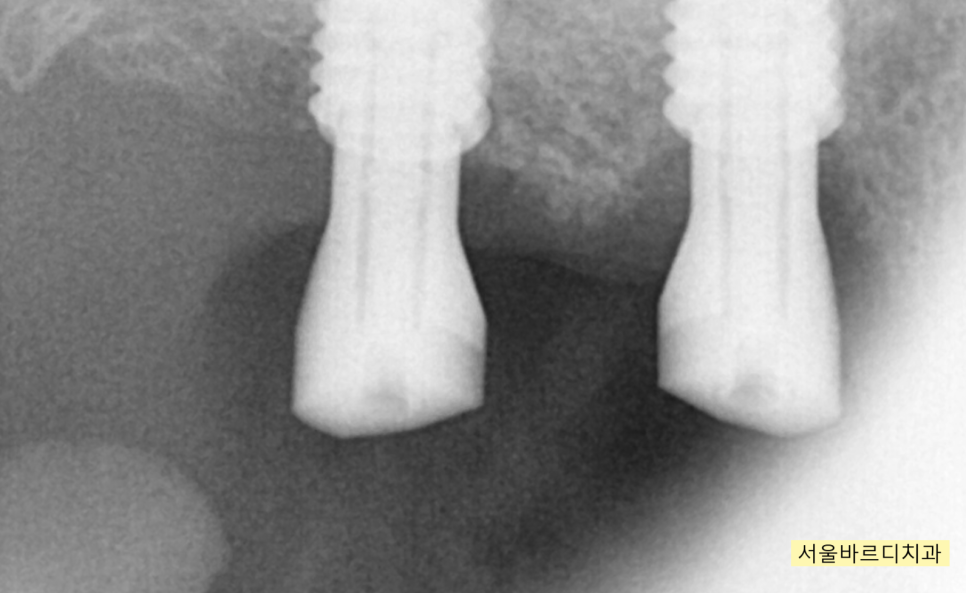

231226

수술 후 3개월 뒤 모습입니다.

임플란트 주변으로 뼈가 둘러싼 모습이 확인 된 후

잇몸을 여는 수술을 진행하였습니다 .